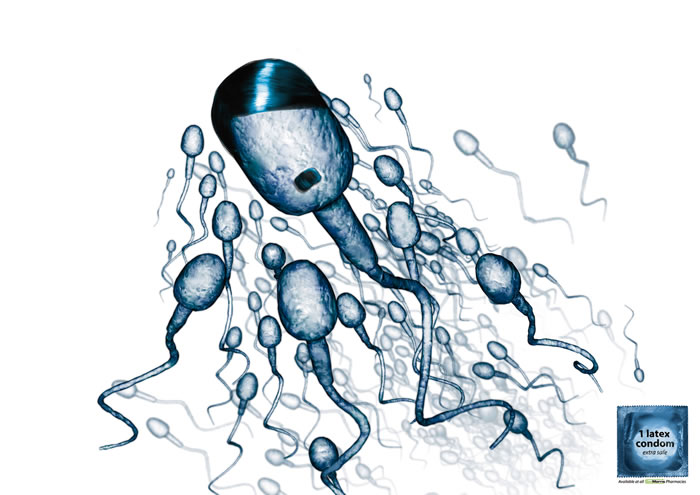

- ·zycazin药品平面广告